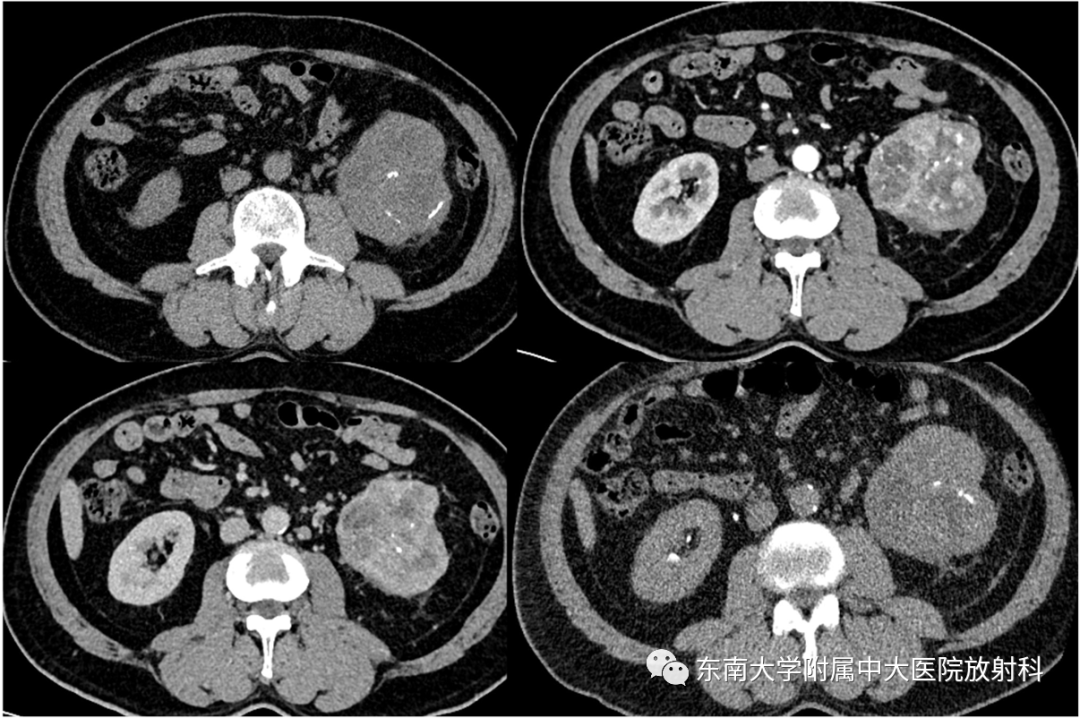

病例2

•男,54岁

•主诉:因肉眼血尿1月来诊。

•体格检查:肾区叩击痛